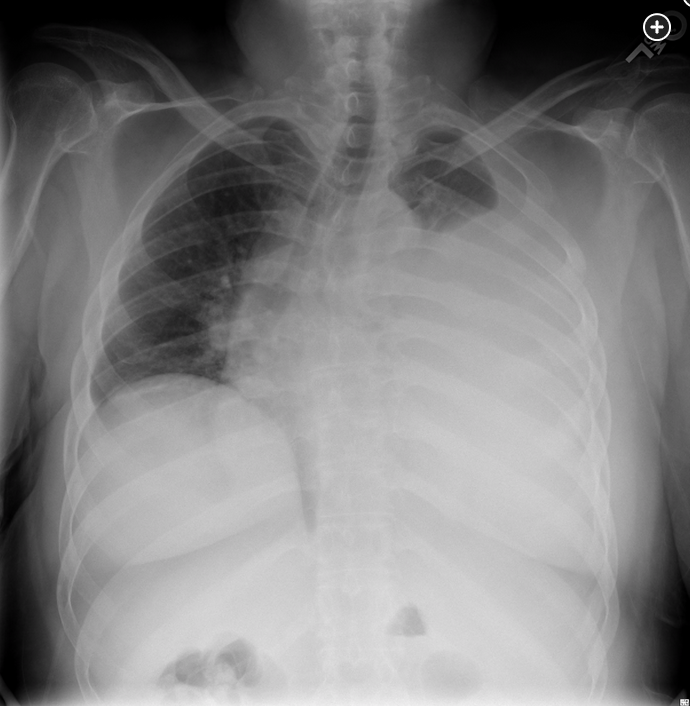

A 44-year-old man was kicked in the chest during an altercation 2 months ago and has had persistent left anterolateral chest wall pain and shortness of breath. He has had no fever or chills. His presenting chest radiograph today is shown (Figure 1). Following tube thoracostomy, 2 L of bloody pleural fluid are removed, and a second chest radiograph is obtained (Figure 2). The hematocrit of the pleural fluid is 10%, while the peripheral blood hematocrit is 43%. The pleural fluid has a pH of 7.15, WBC count of 7,200/μL (7.20 × 109/L), and lactate dehydrogenase of 1,533 U/L (25.60 µkat/L). Gram stain shows no organisms. Over the next 4 h, his shortness of breath worsens. His SpO2 is now 70% on 50% oxygen via face mask. Following emergent intubation, a repeat chest radiograph is obtained (Figure 3). The most likely explanation for this patient’s clinical deterioration is which of the following?